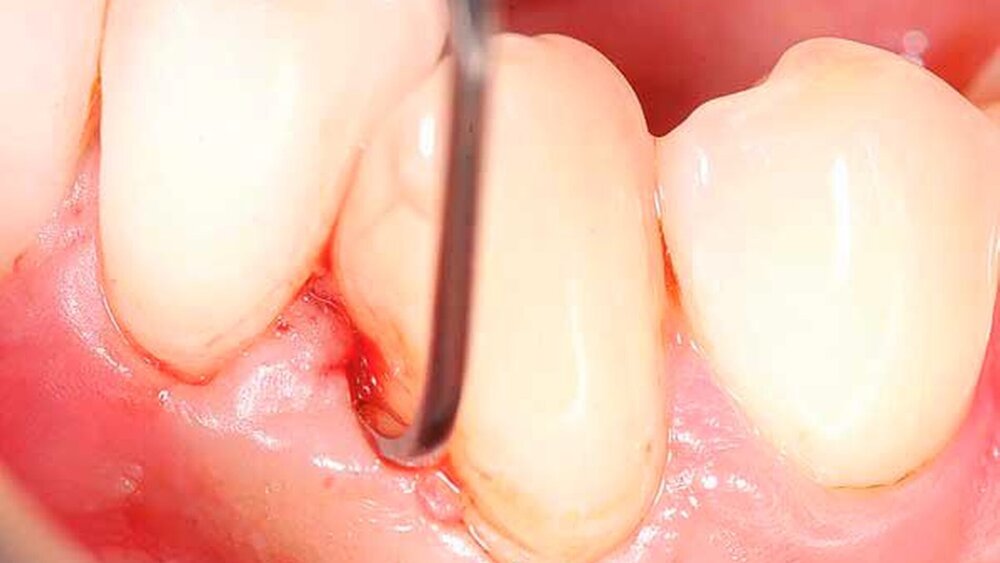

Für die subgingivale Instrumentierung kommen neben Handinstrumenten (wie Gracey-Küretten) auch maschinelle Instrumente mit Schall- oder Ultraschallantrieb infrage. In klinischen Studien zeigte eine Instrumentierung mit diesen Geräten keine deutlichen Unterschiede zwischen den verschiedenen Typen [Tunkel et al., 2002], zweckmäßigerweise können Hand- und maschinelle Instrumente kombiniert eingesetzt werden [Jepsen et al., 2011]. Eine übermäßige Bearbeitung der Wurzeloberflächen im Sinne einer klassischen Wurzelglättung sollte hierbei vermieden werden. Gleichzeitig ist eine Kürettage des Weichgewebes im Regelfall nicht indiziert [Heitz-Mayfield und Lang, 2013]. Neben einer seiten- oder quadrantenweisen Instrumentierung ist auch ein Full-Mouth-Scaling in einem Termin (oder an zwei Terminen innerhalb von 24 Stunden) möglich, allerdings ohne langfristig nachweisbaren klinischen Vorteil [Eberhard et al., 2015].

Von großem Interesse sind derzeit weiterhin subgingival eingesetzte Pulver-Wasserstrahl-Geräte. Mit gering abrasivem Pulver, häufig auf Glycin-Basis, können damit schnell und gründlich Biofilme, aber keine mineralisierten Ablagerungen entfernt werden [Flemmig et al., 2012]. Das Verfahren hat daher seine Stärke im Bereich der unterstützenden Parodontitistherapie, wo in der Regel keine ausgeprägten Konkremente zu erwarten sind. Für einen denkbaren Einsatz während der subgingivalen Instrumentierung liegen noch keine ausreichenden klinischen Daten vor, insbesondere ist wahrscheinlich die dem Verfahren immanente Gefahr eines Luftemphysems bei dem in der ersten Behandlungsphase oft noch stark aufgelockerten Gewebe (vgl. Abbildung 1) noch deutlich erhöht.